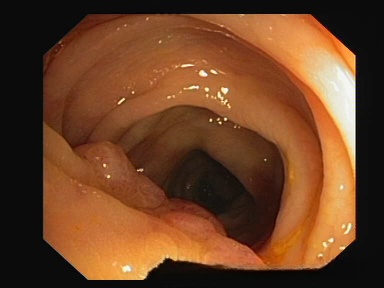

该数据库专为结直肠癌早期筛查提供高质量医学影像数据。该数据库汇聚了丰富的高分辨率内窥镜影像。这些影像经过严格的质量控制流程,并被用来优化自动化诊断算法的性能。该数据库涵盖多种类型息肉及复杂内镜场景

处理好后的COCO格式的数据集图像的总数为380张,类型标签为病灶区域。